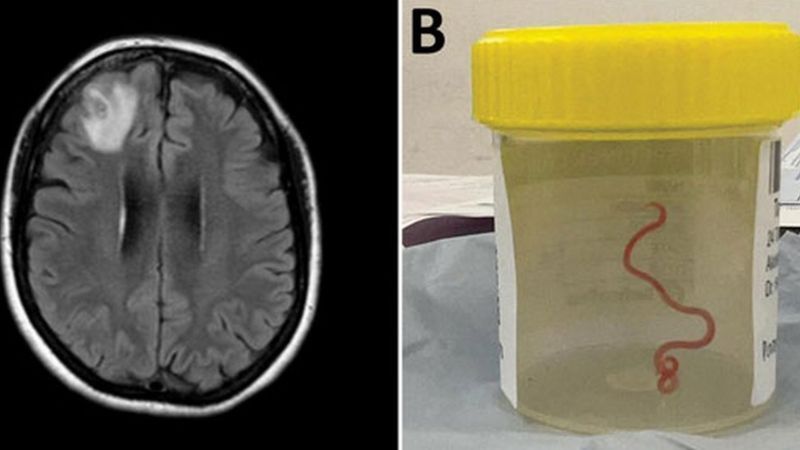

Ammon News - In a world first, scientists say an 8cm (3in) worm has been found alive in the brain of an Australian woman.

The "string-like structure" was pulled from the patient's damaged frontal lobe during surgery in Canberra last year.

She was admitted to hospital in late January 2021, and a scan later revealed "an atypical lesion within the right frontal lobe of the brain".

The red parasite could have been alive in her brain for up to two months, doctors said.

"Everyone [in] that operating theatre got the shock of their life when [the surgeon] took some forceps to pick up an abnormality and the abnormality turned out to be a wriggling, live 8cm light red worm," said Dr Senanayake.